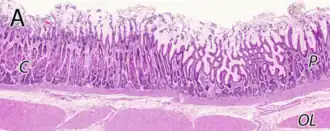

Mediante el microscopio óptico es posible observar algunas características de este micro-órgano multicelular denominado glándula gástrica.

Estas glándulas presentan diferente morfología en los distintos sectores de la capa mucosa del estómago.

En la zona del cardias se muestran más salientes y superficiales, en el fondo (fundus gastrico) zona fúndica u oxíntica, mientras en la zona del píloro son más profundas y largas.